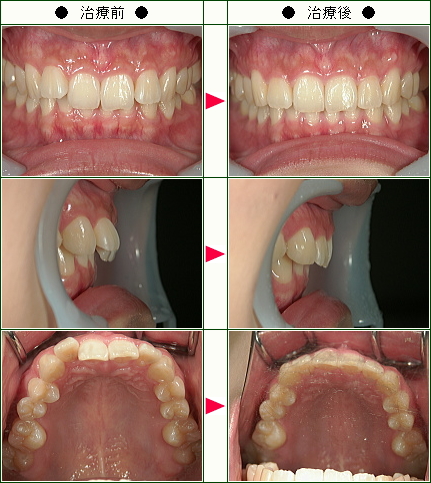

☆歯のデコボコ矯正症例(Y.I様 30歳 男性)

上の前歯が1本が突き出していて、昔から気になっていました。

特にアメリカに留学した際、皆歯並びを気にしているせいか、みんなが綺麗な歯並びで余計気になるようになりました。

ただ矯正は高いというイメージがあり、行動に移せずにいましたが、たまたまインターネットで部分矯正を知り、値段的にも前歯だけ治せれば良いという、意識的にも自分にぴったりだと思い、今回矯正することにしました。

・感想

治療していただくことで綺麗な歯並びとなり、歯を出して笑うことが多くなりました。